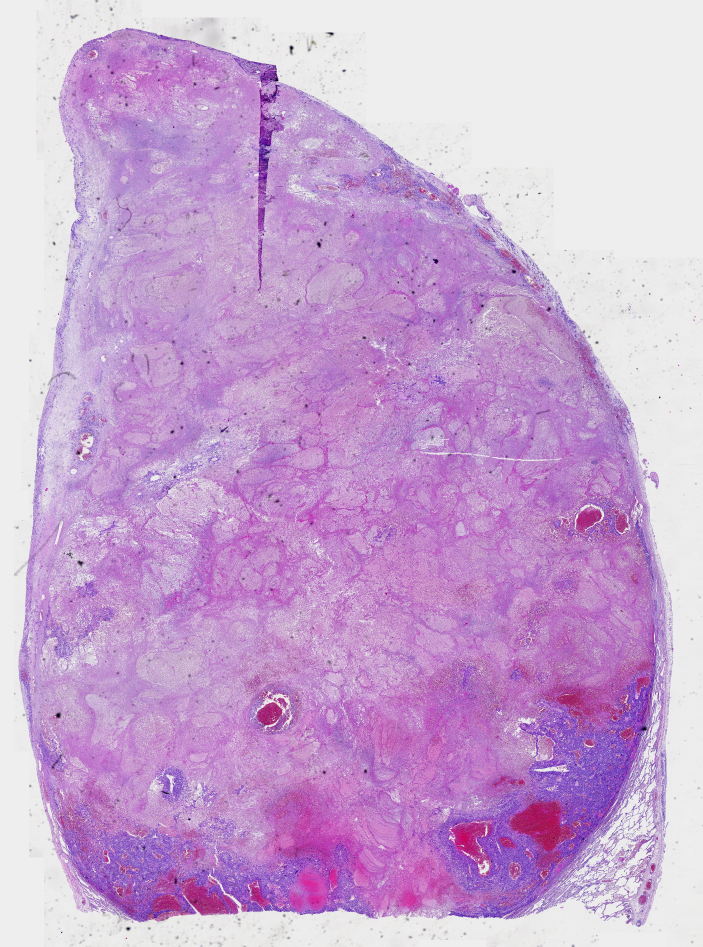

Diffuse sclerosing papillary thyroid carcinoma DSV-PTC typically presents with diffuse thyroid involvement affecting both lobes, marked stromal fibrosis, squamous metaplasia, numerous psammoma bodies, lymphocytic infiltration